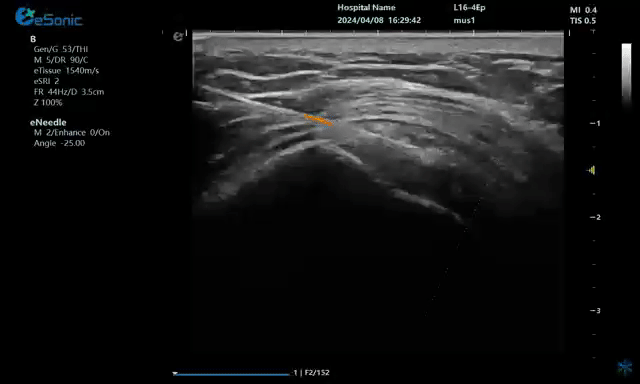

病例:冈上肌肌腱钙化穿刺治疗

注射麻醉药

注射药物

无磁导航技术引导穿刺钙化点